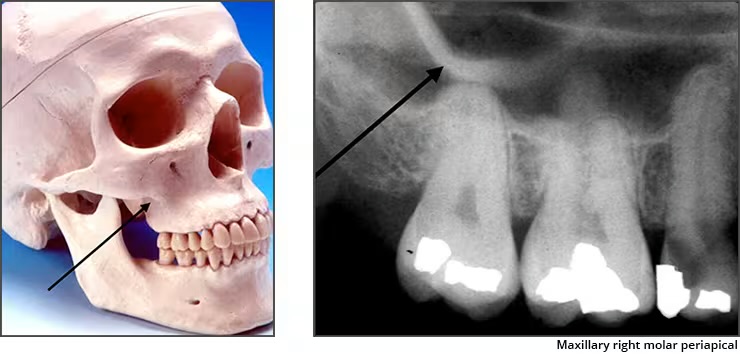

Zygomatic Process (malar process)

Radiopaqe U-shaped structure representing where the zygomatic bone attaches to the maxilla

Seen on maxillary premolar and molar PA’s